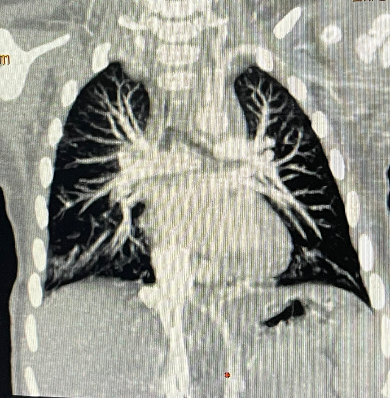

术后1周复查胸部X线,无明显异常